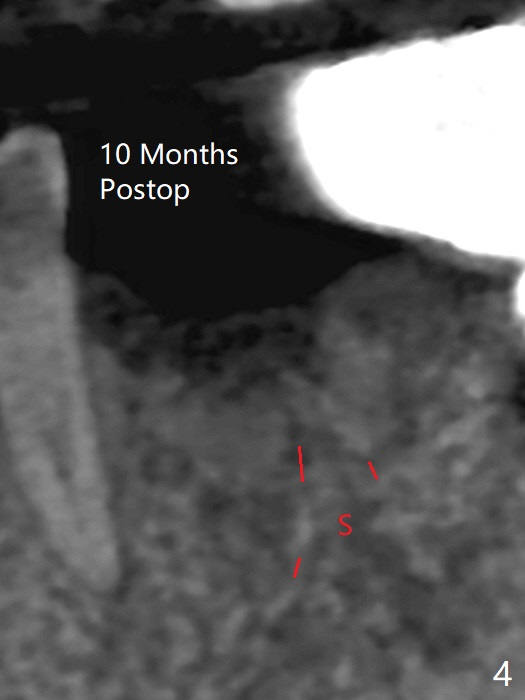

A 58-year-old man requests extraction of the tooth #19 with supraocclusion (Fig.1). After extraction, the septal gingiva has to be sectioned to remove underlying granulation tissue thoroughly. The buccal plate is missing. Ossogen (allograft, Fig.2 *) is placed around the septum (red dashed line). The socket opening is covered by BioXclude and approximated with 4-0 PGA suture, followed by periodontal dressing. With the septum's support, bone graft is expected to heal without too much ridge collapse. The mesial and distal sockets behave as 2 small premolar ones, getting ample blood supply. The socket heals in 20 days (Fig.3). The sockets heal with preservation of the septum (Fig.4: S), while there is formation of the cortical plate on the top of the ridge 10 months postop (Fig.5: ^). It is safe to place a 5x10 mm implant with guide (Fig.6), whereas it may be necessary to place bone graft lingual to the implant at #18 associated with free hand surgery (Fig.7: >). Return to Lower Molar Immediate Implant, No Deviation 18 种植 位点保存 Xin Wei, DDS, PhD, MS 1st edition 01/22/2020, last revision 07/03/2021